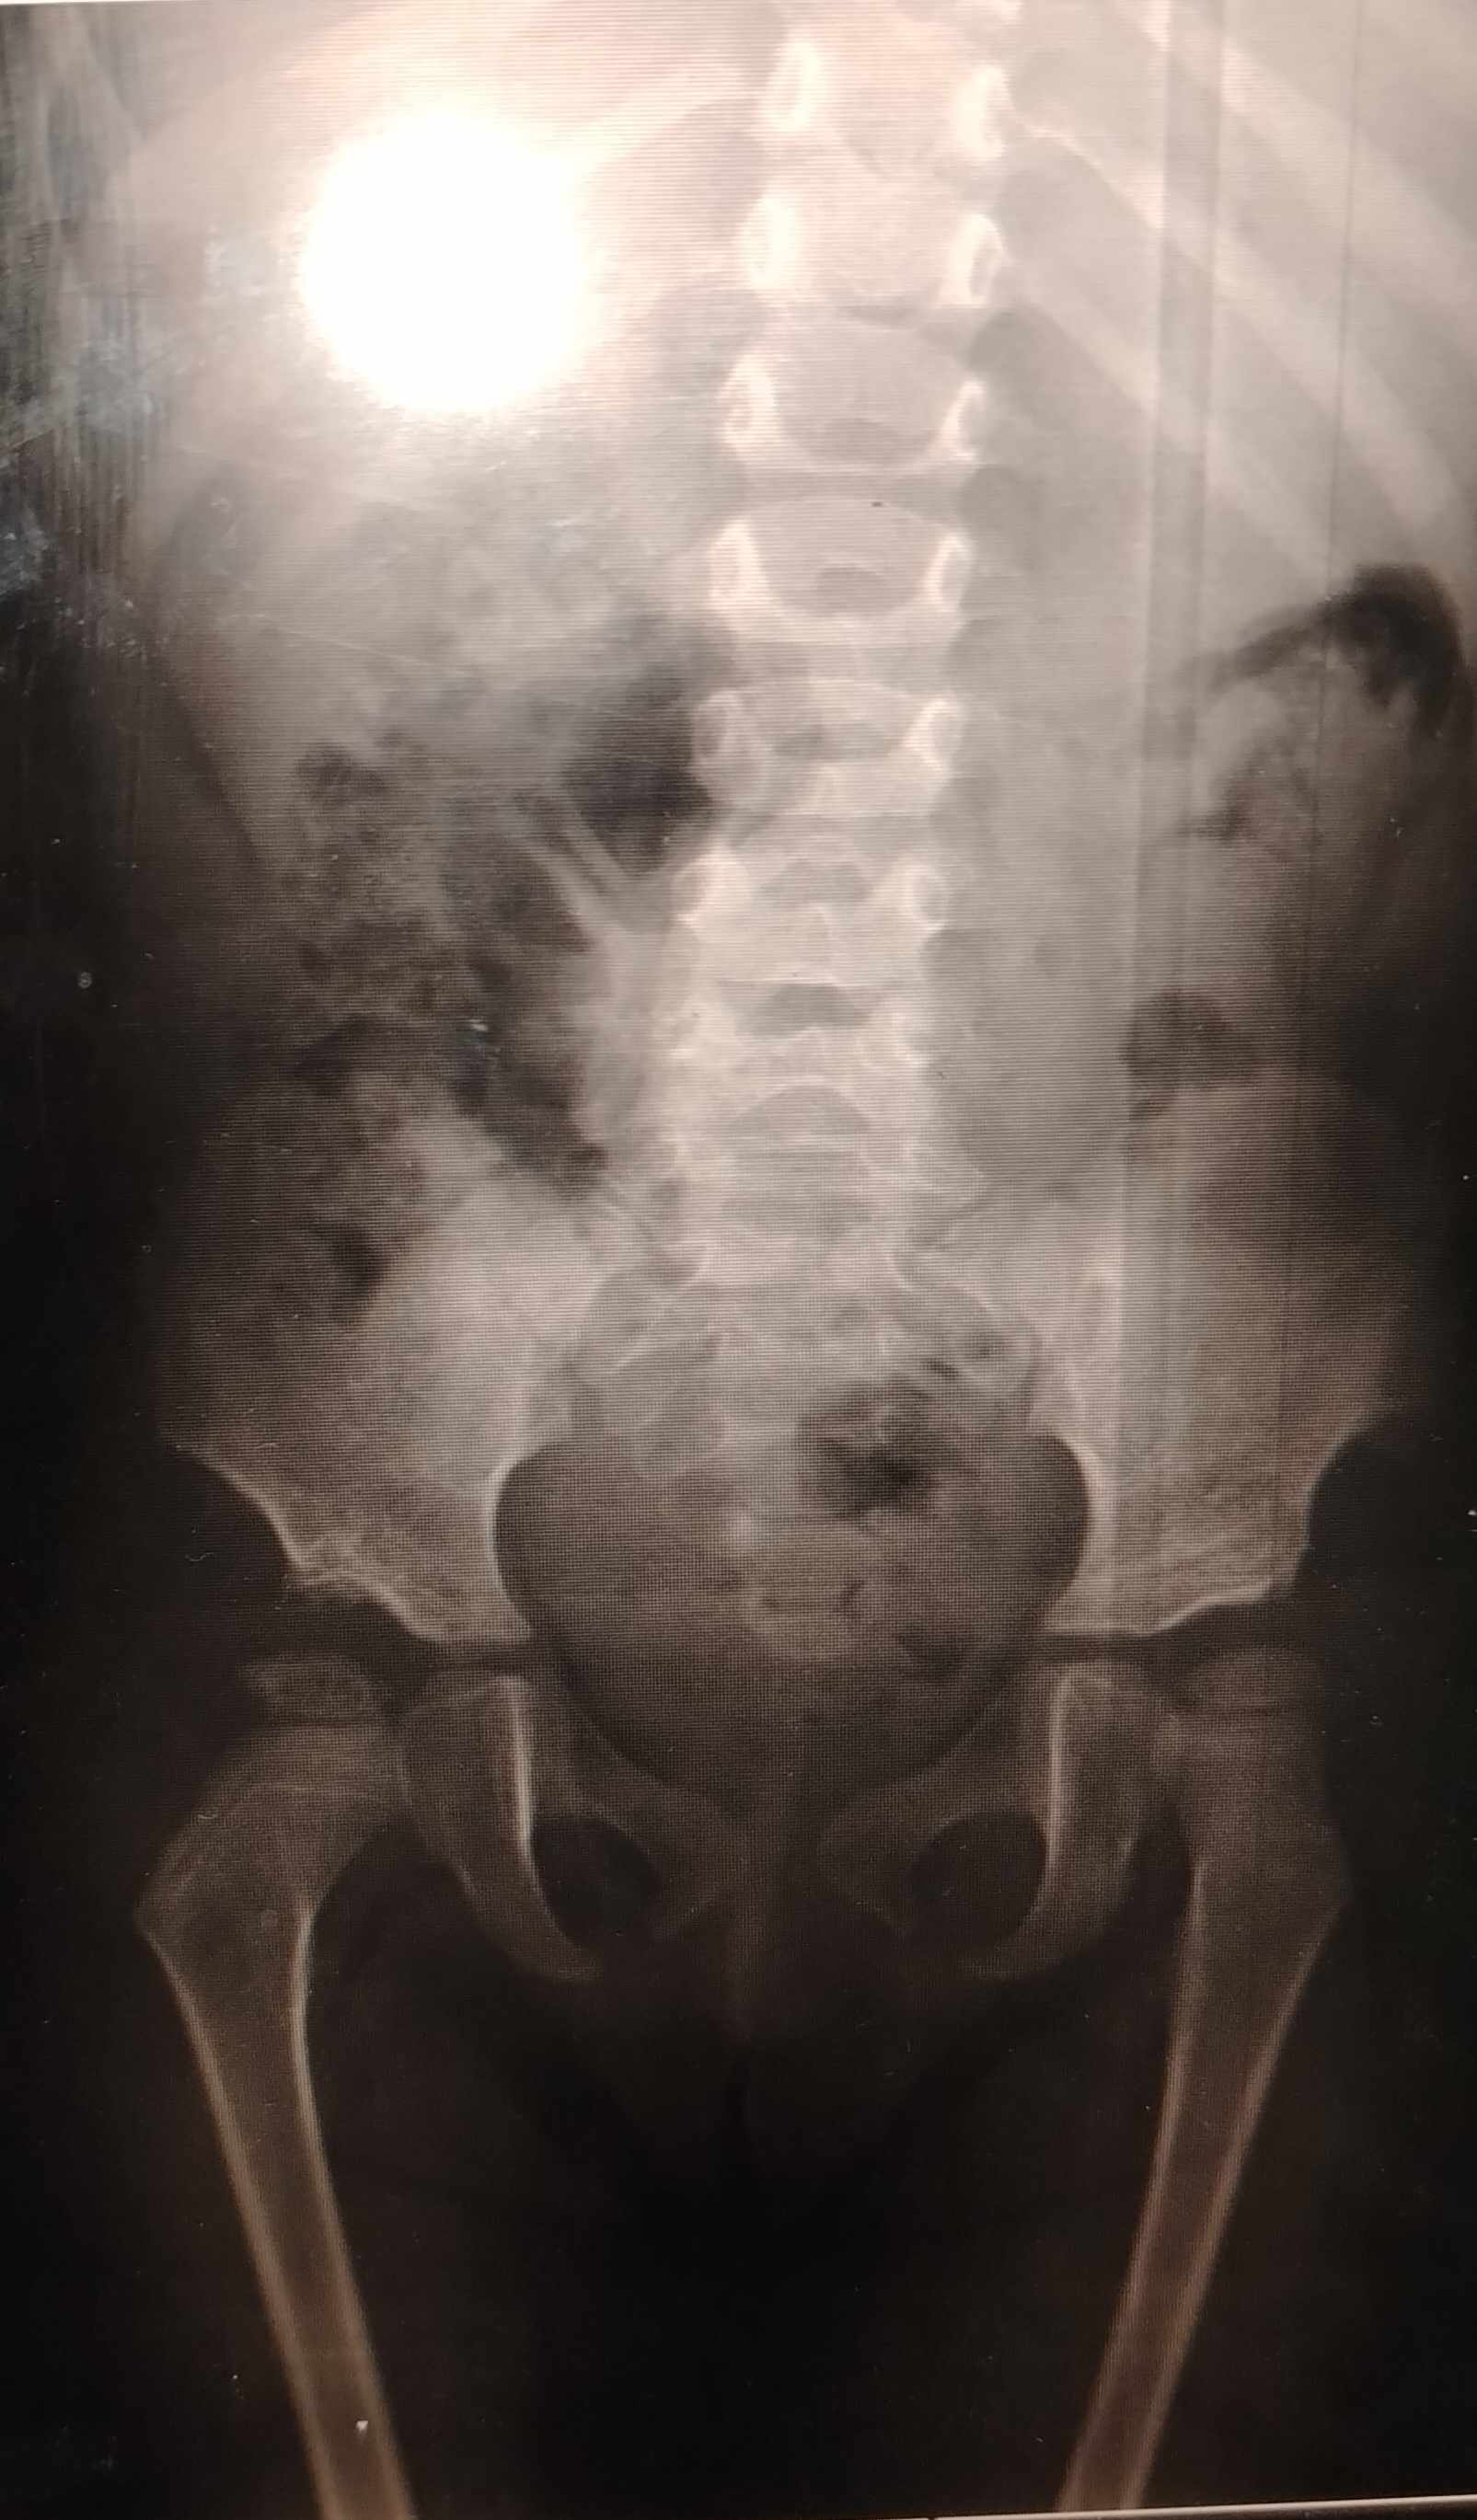

شاهدت الصورة

ولا يوجد أي علامات للخلع بالجهتين

ووضع المفصلين طبيعي

ووضع رأس الفخذ بالجهيتن جيد

وتطور نواة عظم الفخذ جيدة التطور